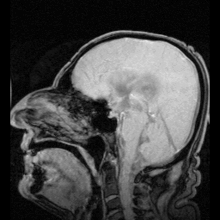

Cerebrospinal fluid (CSF) is a clear, colorless body fluid found in the brain and spine. It is produced in the choroid plexuses of the ventricles of the brain. It acts as a cushion or buffer for the brain's cortex, providing basic mechanical and immunological protection to the brain inside the skull. The CSF also serves a vital function in cerebral autoregulation of cerebral blood flow.

The CSF occupies the subarachnoid space (between the arachnoid mater and the pia mater) and the ventricular system around and inside the brain and spinal cord. It constitutes the content of the ventricles, cisterns, and sulci of the brain, as well as the central canal of the spinal cord.